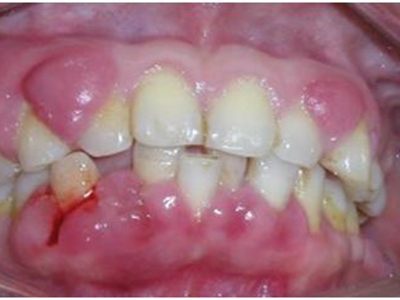

慢性龈炎又称边缘性龈炎或单纯性龈炎,主要表现为游离龈和龈乳头因炎性水肿,而变为鲜红或暗红色,龈缘变厚,龈乳头圆钝肥大。慢性龈炎的患病率高,治愈后仍可复发,部分患者可发展成为牙周炎。

慢性龈炎的病损部位一般局限于游离龈和龈乳头,以前牙区为主,尤其以下前牙区最为显著,患者常因刷牙或咬硬物时牙龈出血而就诊。游离龈和龈乳头颜色变为鲜红或暗红色,病变较重时炎性充血可波及附着龈。龈缘变厚,龈乳头圆钝肥大,可增生呈球状,覆盖牙面。牙龈松软脆弱,缺乏弹性。